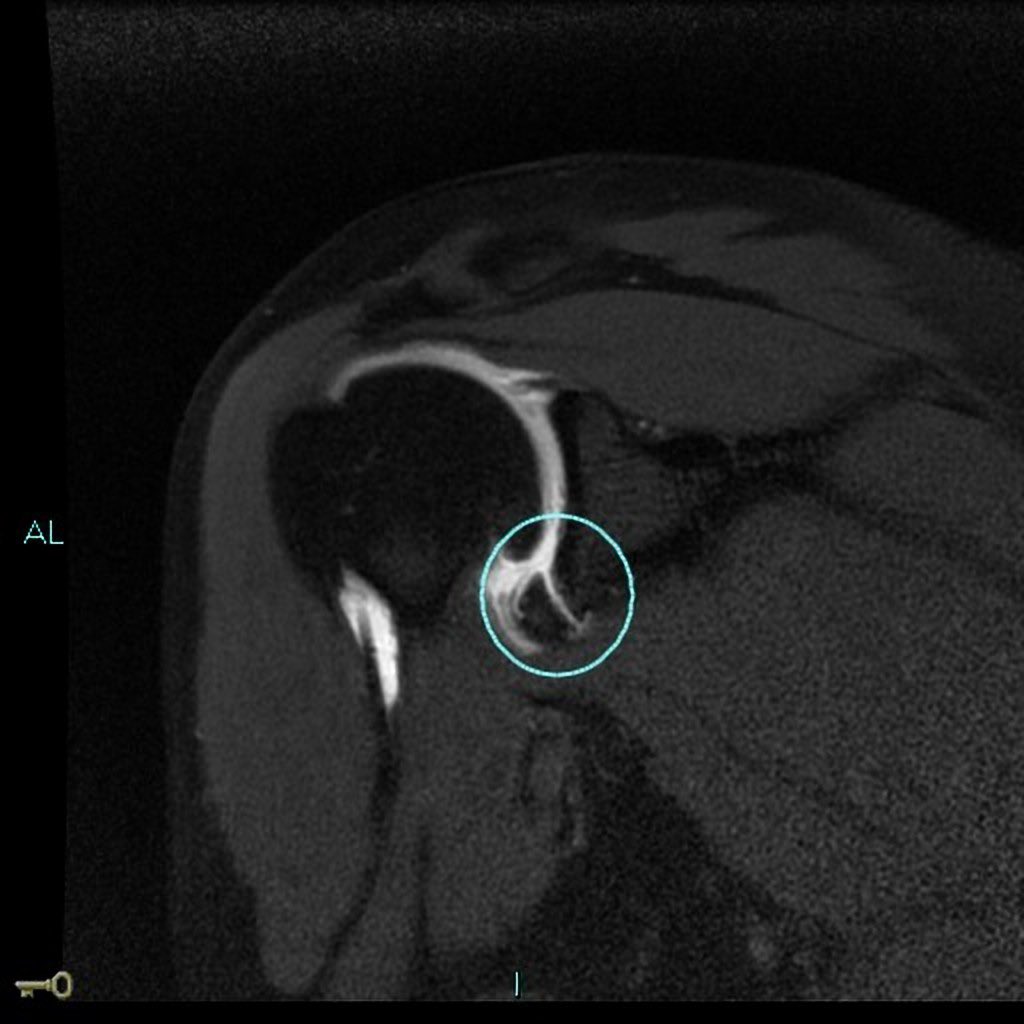

عندما يحدث هذا، يتشكل تجويف في مقدمة الحقاني الذي يسمح لرأس عظمة العضد بالانفصال فيه. 💡

معلومة 📍"سميت آفة بانكرت على اسم جراح العظام آرثر سيدني بلونديل بانكرت."

عادةً ما يتم إجراء إصلاح آفة بانكرت بالمنظار. يهدف لإصلاح وشد الأربطة المتمددة والمتضررة وكبسولة المفصل والغضاريف.